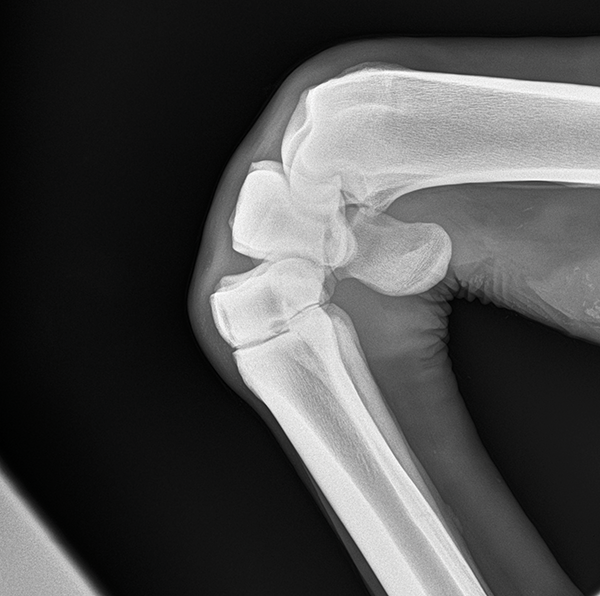

mediolateral projection of the elbow

flexed mediolateral projection of the elbow